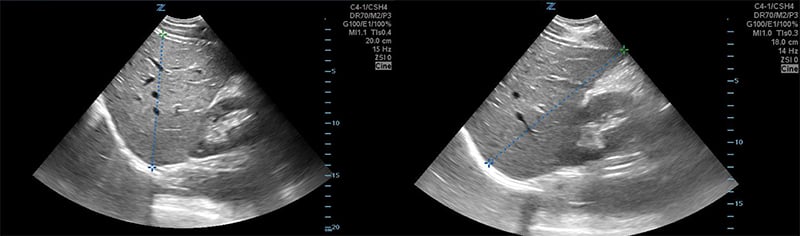

Figures 24B & 24C. Large pyogenic liver abscess with heterogenous material swirling inside the lesion, measuring >11cm in the long dimension (B) and >5cm in the shorter dimension (C).